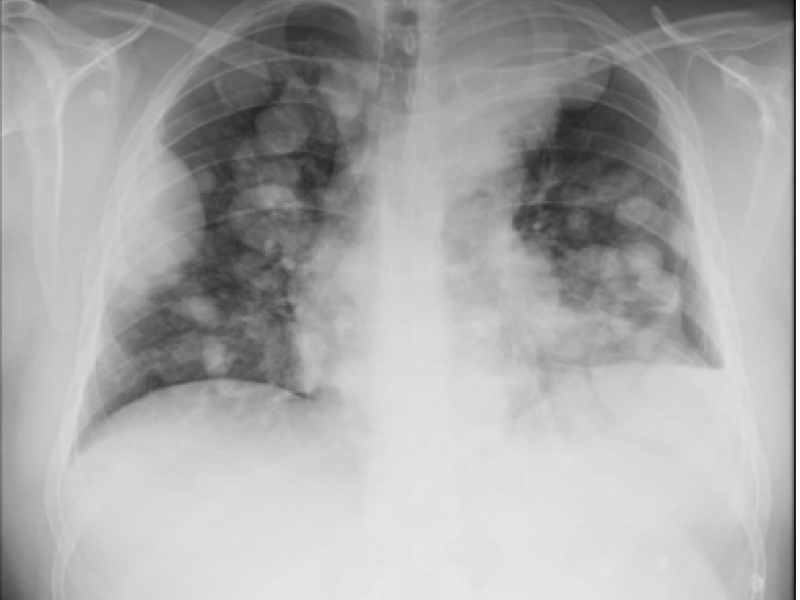

A patient comes into the ED with a high fever, shortness of

A 27 yo M with a PMHx of osteosarcoma s/p R hip